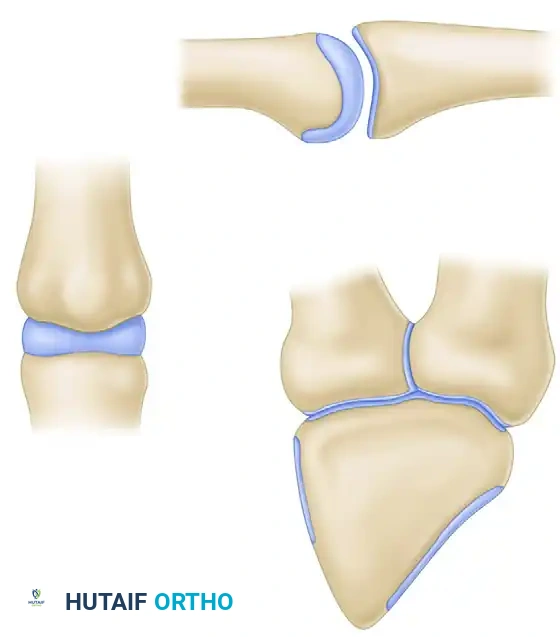

PROXIMAL INTERPHALANGEAL (PIP) JOINT FRACTURE-DISLOCATIONS

A PIP joint fracture-dislocation is a devastating injury that, as a rule, results in an unstable dorsal displacement of the middle phalanx. This pathoanatomy is caused by the disruption of the attachment of the volar fibrocartilaginous plate, often taking a fragment of the volar lip of the middle phalanx with it.

- Large Single Fragment (>50% Articular Surface): If a large, single volar fragment involving more than 50% of the joint surface is present, ORIF is indicated. Fixation can be achieved with one or more K-wires, minifragment screws, or a wire loop pullout technique.

- Small Fragments (<50% Articular Surface): If the fragment or fragments include less than 50% of the articular surface, the technique described by McElfresh, Dobyns, and O’Brien is preferred. This utilizes an extension block splint, allowing active flexion of the PIP joint while preventing the terminal extension that leads to dorsal subluxation. This gives satisfactory results, especially in cases without gross displacement.

- Chronic/Persistent Subluxation (≤40% Articular Surface): For persistent dorsal fracture-dislocations with preserved condyles of the proximal phalanx and a volar defect of 40% or less, the volar plate arthroplasty method of Eaton and Malerich may be used. They reported successful use of this technique in old, healed, displaced fractures even 2 years after injury.

A size-matched segment of the distal hamate articular surface is carefully shaped to match the comminuted contour of the middle phalanx. The distal hamate (articulating with the base of the 4th and 5th metacarpals) possesses a central ridge that perfectly mimics the median ridge of the middle phalangeal base, providing exceptional coronal plane stability.